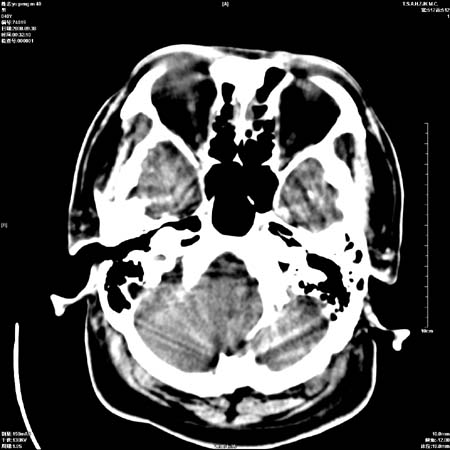

以下是引用zjzjr在2008-10-4 20:29:00的发言:[br]右颞叶皮质区密度略减低,脑沟较对侧变浅,考虑早期脑梗塞,建议mri.左侧小脑幕缘旁可见带状低密度影,轻度占位效应,支持蛛网膜囊肿,枕大池区亦考虑蛛网膜囊肿.